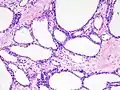

Micrograph showing a pancreatic serous cystadenoma. H&E stain.

Pancreatic serous cystadenoma